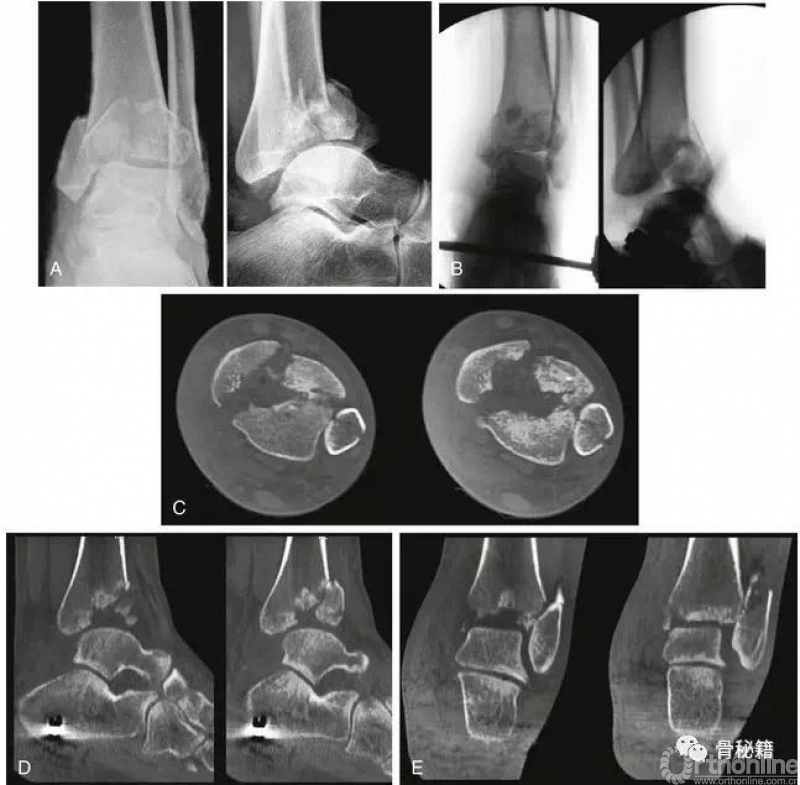

六、具体病例手术技术举例与细节12步

1. 显露关键骨块!通过外旋转内踝骨片并通过施加牵引,可以看到粉碎的中央关面。

2. 别着急复位!先找标兵!在确定所有粉碎块后,通过没移位的后外侧骨块作为pilon关节复位的关键来进行复位。如果后外侧骨块移位,应考虑通过使用后外侧切口来稳定这种情况。如果胫腓前韧带和胫腓后韧带是完整的,那么复位腓骨后,则该骨块应该处于解剖位置。

3. 临时固定 使用克氏针将关节面拼接在一起,尽量完成拼图游戏,通过在两个或三个较大的片段之间楔入可以复位的小片段。当表面重建后,暂时固定内踝。

4. 透视在透视中得到较好的正位,侧位,并在需要时透视踝穴位。进行复位效果的评价和分析。

5. 关节面--干骺端一旦关节面复位满意,就可以进行干骺端的复位。在简单的骨折中,不需要骨移植,事实上,如果植骨太多有时也会使得复位不良。

按照以上的完整步骤,术后CT显示复位较好。